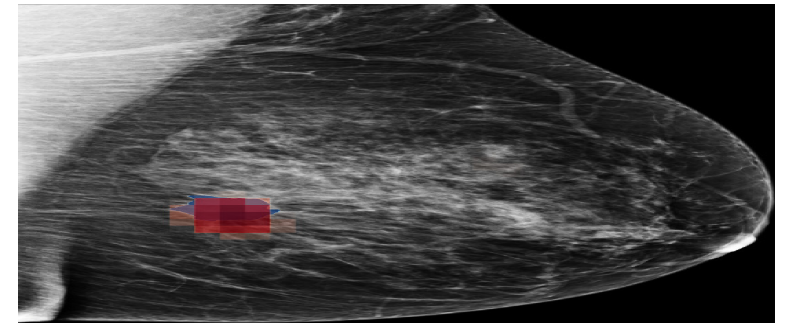

Refer to caption

(a) NYUtr\mathcal{M}_{\mathrm{NYU}}^{\mathrm{tr}}

(b) HCTPtr\mathcal{M}_{\mathrm{HCTP}}^{\mathrm{tr}}

(c) HCTP(BNFC)tr\mathcal{M}_{\mathrm{HCTP(BNFC)}}^{\mathrm{tr}}

Figure 12: Saliency maps generated by NYUtr\mathcal{M}_{\mathrm{NYU}}^{\mathrm{tr}}, HCTPtr\mathcal{M}_{\mathrm{HCTP}}^{\mathrm{tr}}, HCTP(BNFC)tr\mathcal{M}_{\mathrm{HCTP(BNFC)}}^{\mathrm{tr}} models a sample from the HCTP dataset. Blue regions represent the ground truth annotations, while red regions highlight the saliency maps corresponding to the malignant class.

The saliency map in Figure 12 further supports these findings, showing that HCTP(BNFC)HCTPtr\mathcal{M}_{\mathrm{HCTP(BNFC)}\rightarrow\mathrm{HCTP}}^{\mathrm{tr}} highlights similar regions of interest as the fully fine-tuned model (HCTPtr\mathcal{M}_{\mathrm{HCTP}}^{\mathrm{tr}}).